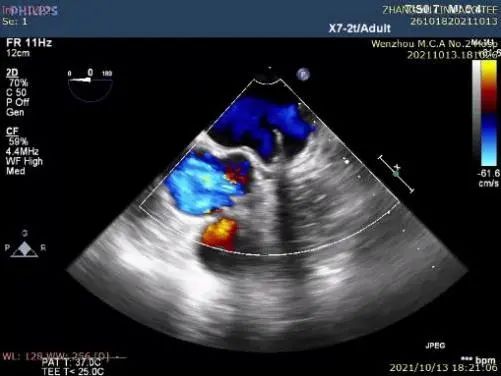

②左心耳封堵

行左心耳头位和足位造影,造影显示左心耳为菜花型。锚定区约为20mm,开口区约为24mm,依据选型原则,拟选LAmbre™2228封堵器或2430封堵器。

图1:RAO30° CRA20° 头位造影

图2:RAO30° CAU20° 足位造影